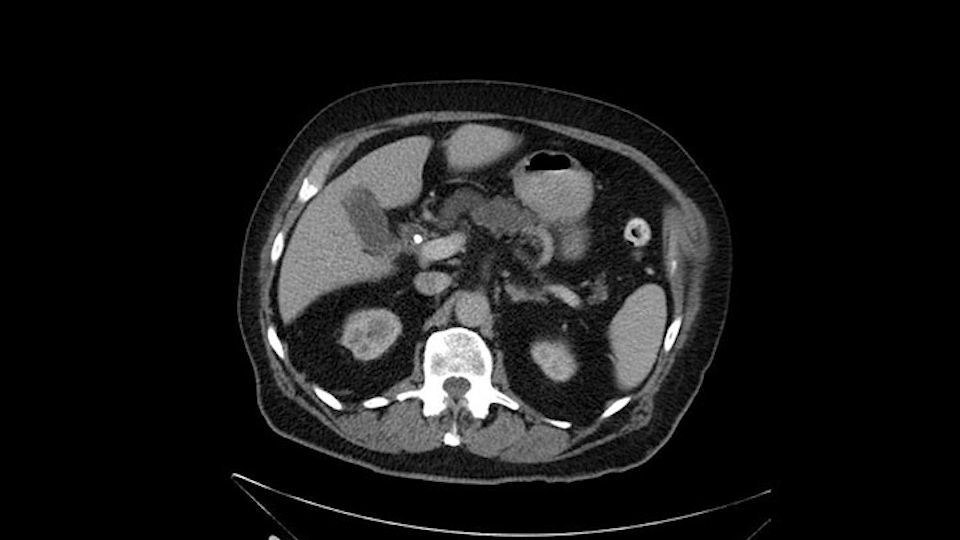

He has no liver metastases or obvious metastatic disease. On reviewing his CT scan, he has normal vascular anatomy; he has no involvement of the portal vein by the looks of it, or the superior mesenteric vein.

He has normal arterial anatomy: no accessory or replaced right hepatic artery, which is important because sometimes the right hepatic artery can come behind the neck of the pancreas and you have to be careful of that in a Whipple dissection.

The next item that I would look at: the issue would be the vessels and usually start at the portal vein, watch the portal vein, follow it down, down-down-down to the neck of the pancreas - which is here - and there’s no impingement by tumor, which is great. The SMV and the splenic vein, which is here. The splenic vein junction is normal, which is great.